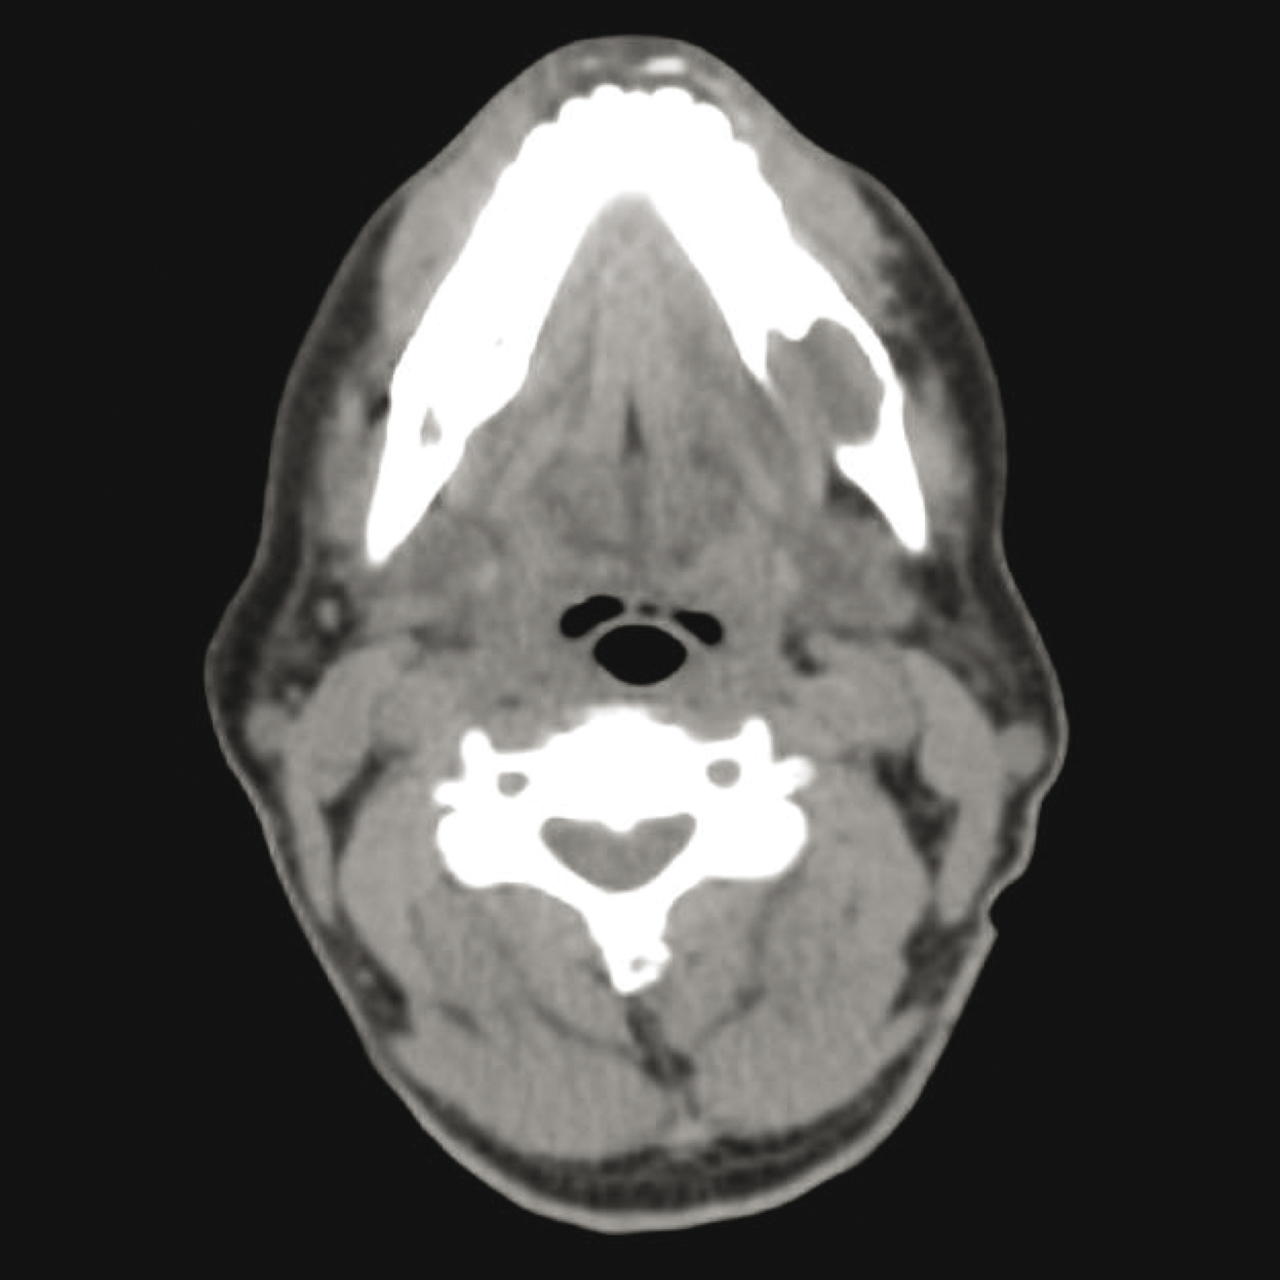

Quel est votre diagnostic ? Ostéonécrose mandibulaire Plasmocytome Il s'agit d'un plasmocytome. Pour en savoir plus :- Fermand JP et al. Dossier "Gammapathies monoclonales". Rev Prat 2018;68(7):775-803. - Fain O, Braun T, Winterman S, Agranat P. Plasmocytome. Rev Prat 2008;58(19):2097. Granulome éosinophile Sarcoïdose Carcinome mandibulaire OK Valider mes réponses